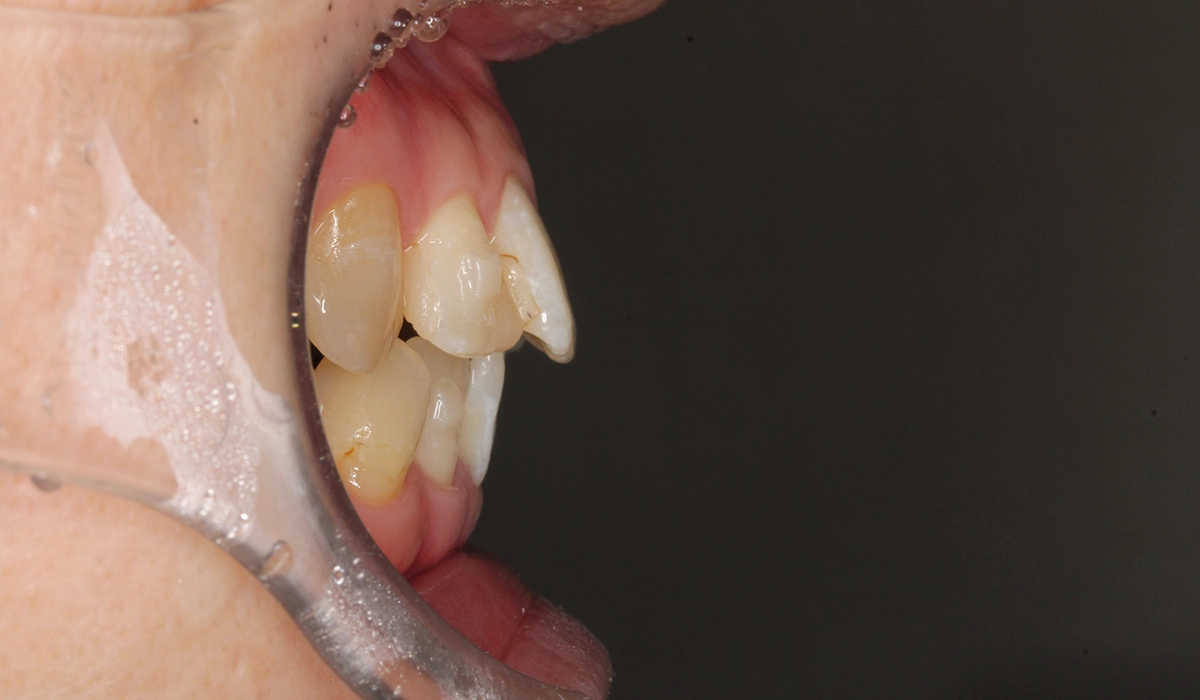

術前:右側

術後:右側